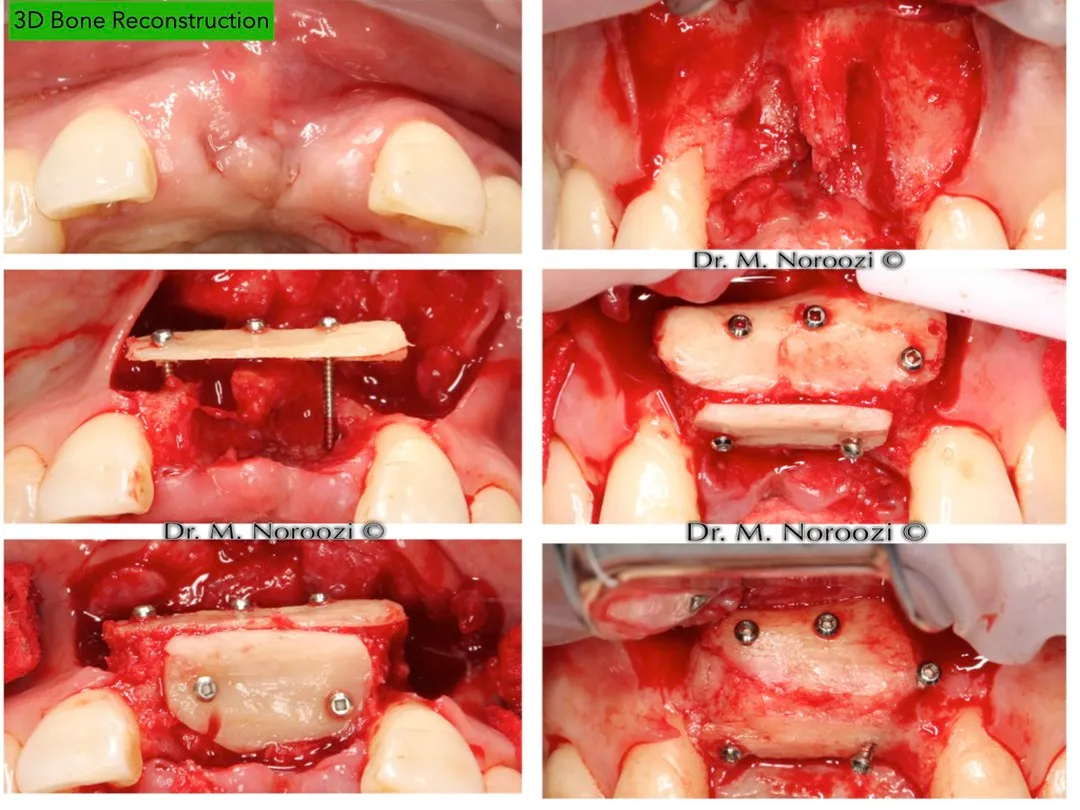

“Beyond Repair: Transformative Bone Grafting and Implant Therapy for Devastating Anterior Teeth Loss”

Dr Noroozi IMPrESS Perio Implant Center Bone Grafting for Dental Implants Khoury Technique